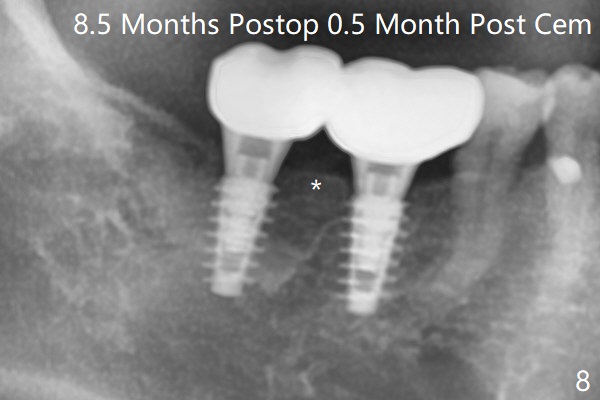

54岁男,右下6,7位点保留后7个月回来植牙,植牙床是个平面(图一),今后两个牙齿之间龈乳头一定缺乏,如何重建?放置导板,稍微使用环形钻头,在6,7植牙床上形成标记(图二),然后切开,植入植体,6扭力低,7高,所以安置愈合(6x5毫米)和修复(5.5x4(4)毫米)基台。原来导板设计把植体植入牙槽嵴(图三:白虚线)下1-2毫米,自动提高植体间牙槽嵴,接着把钻洞产生的骨粉放在后者上缘(*),由近中和远中基台固定。最后覆盖胶原膜,缝合(图四)。原来导板需要切除的角化龈保留住了(图四:7B,7L)。放入修复基台目的是利用它的高度固定牙周敷料。术后3个月7牙槽窝愈合(位点保存后10个月,图五:*),植体间牙槽嵴仍旧高(箭头),6放置修复基台,准备做临时牙冠。右上7反合,需要做局部矫正(图六)。病人非常感激术后三个月制作的临时牙冠(连体)。术后五个月对临时牙冠进行修改:6牙合面垫高(图七:*),这样上下7牙合面分开,上7颊侧放置矫正器,下7牙圈(舌侧有cleat),两者之间安置橡皮筋,上7就可以自由往舌侧移动。术后8.5个月全景片和CT显示植体种植牙槽嵴下(图八至十),这也是重建龈乳头基础。